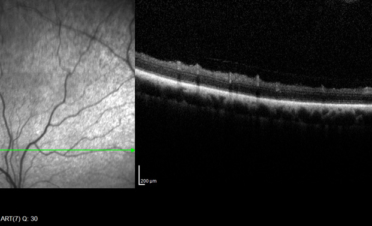

- Retinografía o fotografía de ambas retinas para estudiarlas con mayor detenimiento.

- OCT de retina para ver la estructura del complejo retina-coroides y detectar anomalías como microdesprendimientos, exudados en retina, etc No se observaron anomalías en la retina de ningún ojo, solo un ligero engrosamiento de la coroides en el ojo derecho (el más afectado).